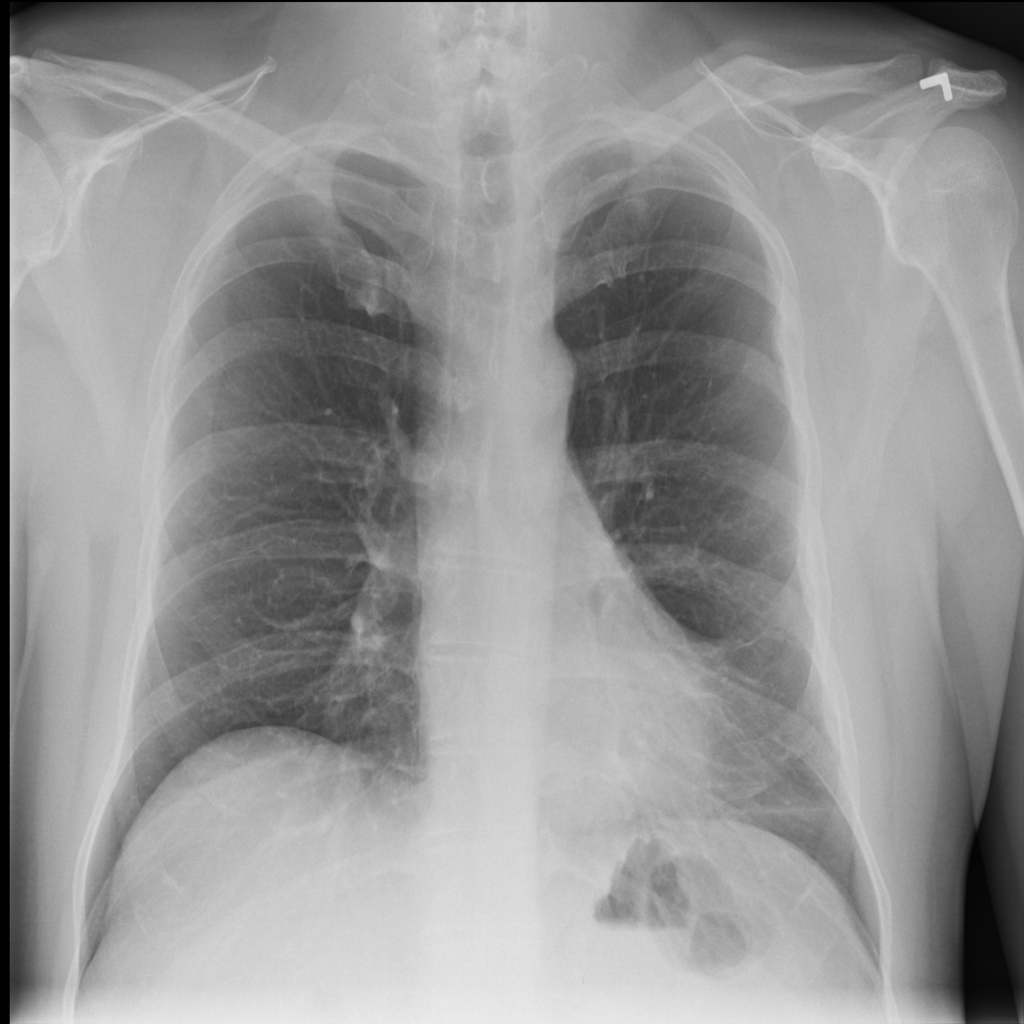

PAT-1F50 · IMG-000Fibrosis

PAT-1F50 · IMG-000

PA